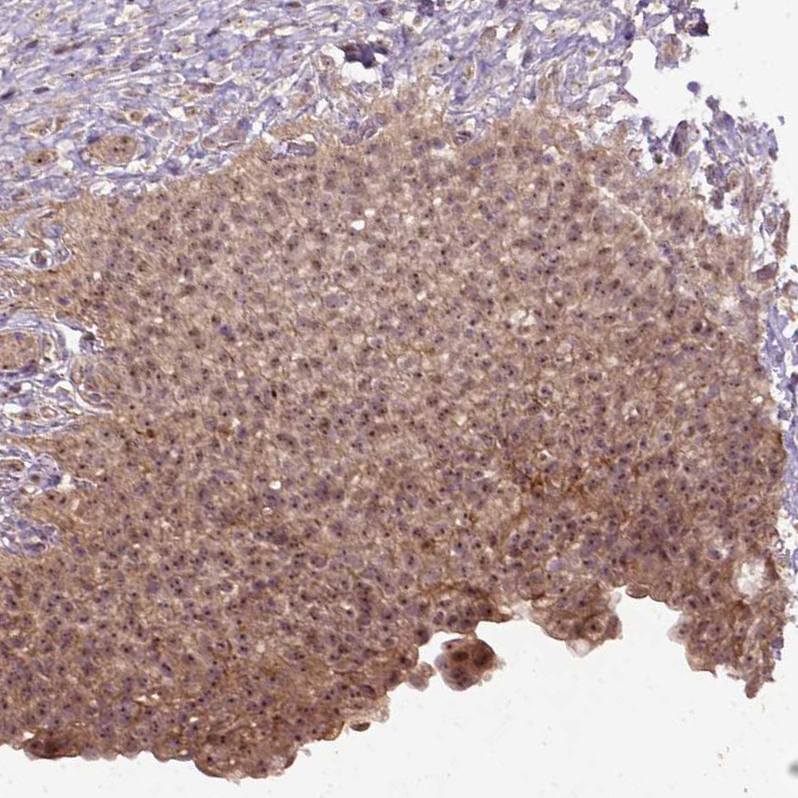

Immunohistochemical staining of human urinary bladder shows moderate positivity in nucleoli in urothelial cells.